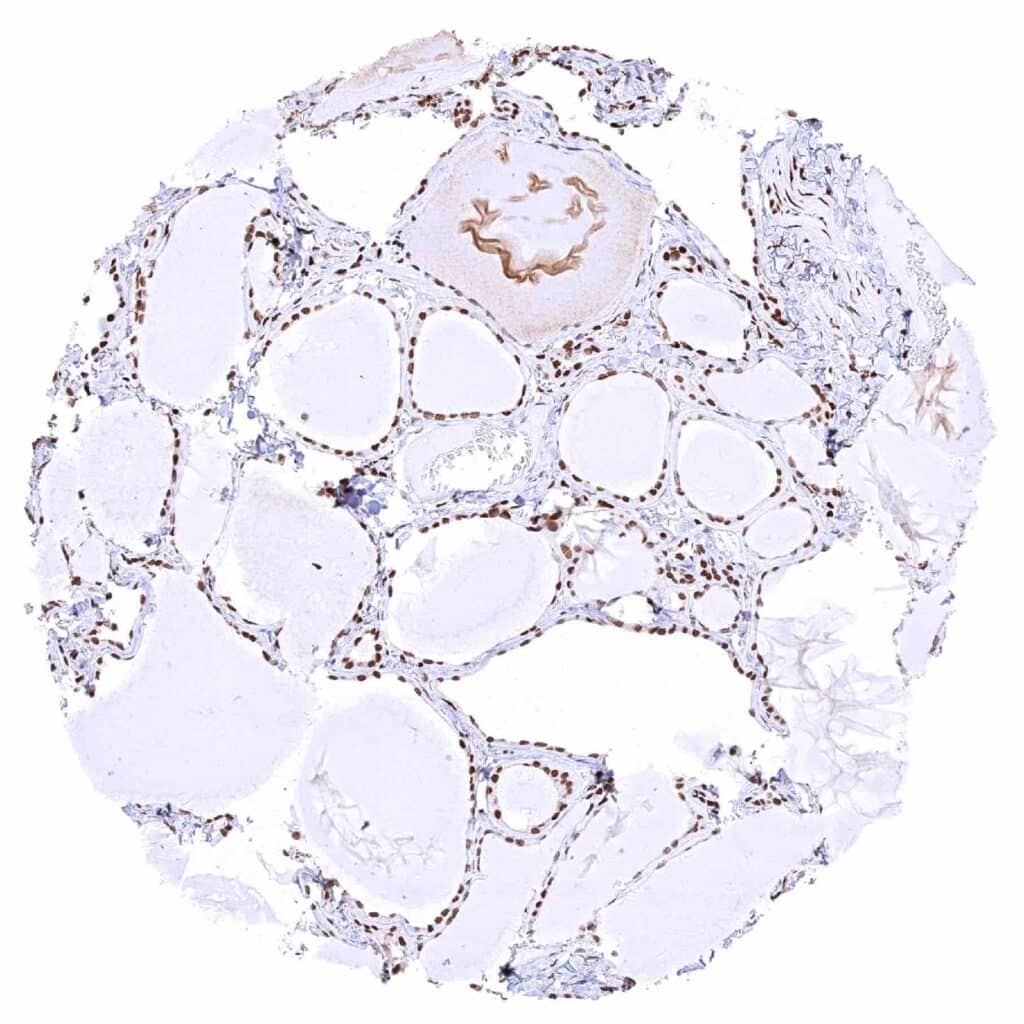

Thyroid gland – Strong nuclear MRE11 staining of follicular cells